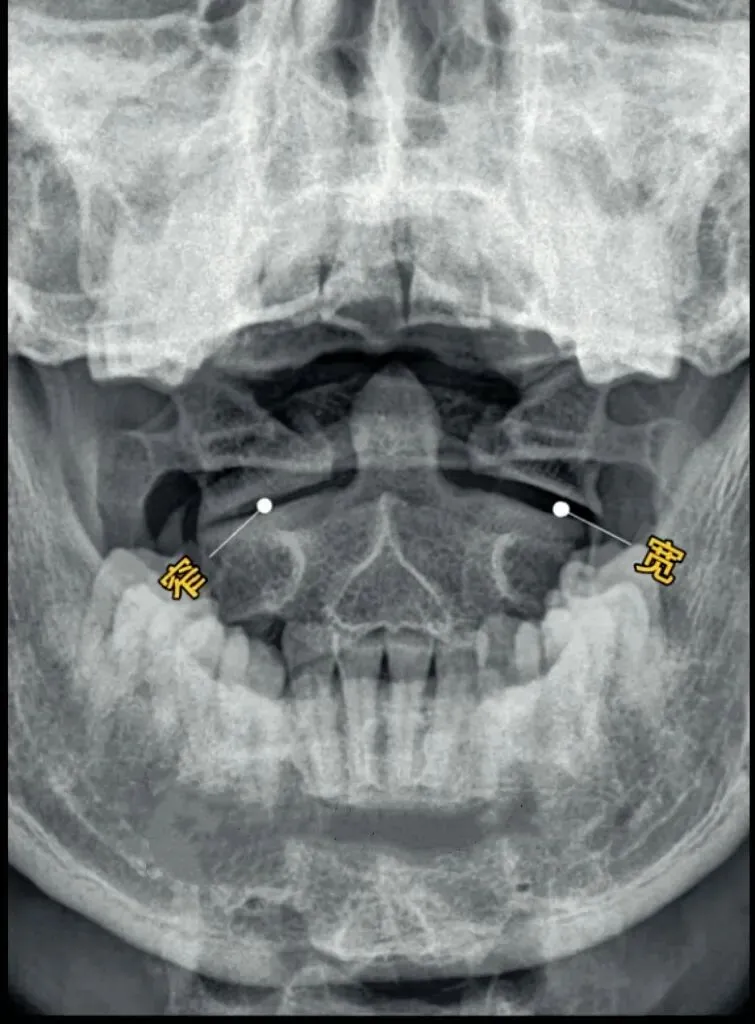

十张口是指寰枢椎的结构和位置关系,我们主要观察寰齿间隙和寰枢关节间隙及寰椎侧块的大小,来判断寰枢关节有无脱位的情况。

首先是寰齿间隙,如果枢椎与颈三的棘突位于同一条直线,

那么寰齿间隙哪边宽,就代表寰椎向哪边发生了侧方移位。

如果不在一条直线上,那就代表枢椎也有侧向的移动或旋转。

接下来是寰枢关节间隙,也称寰枢外侧关节,主要看两侧间隙是否等大,

如果一边宽一边窄,就代表寰椎向窄的一方发生了侧向倾斜。

再下来看寰椎侧块的大小,正常情况下侧块两边的宽度是等大的,

如果哪边侧块变大,就代表哪边的侧块向前方发生了旋转。